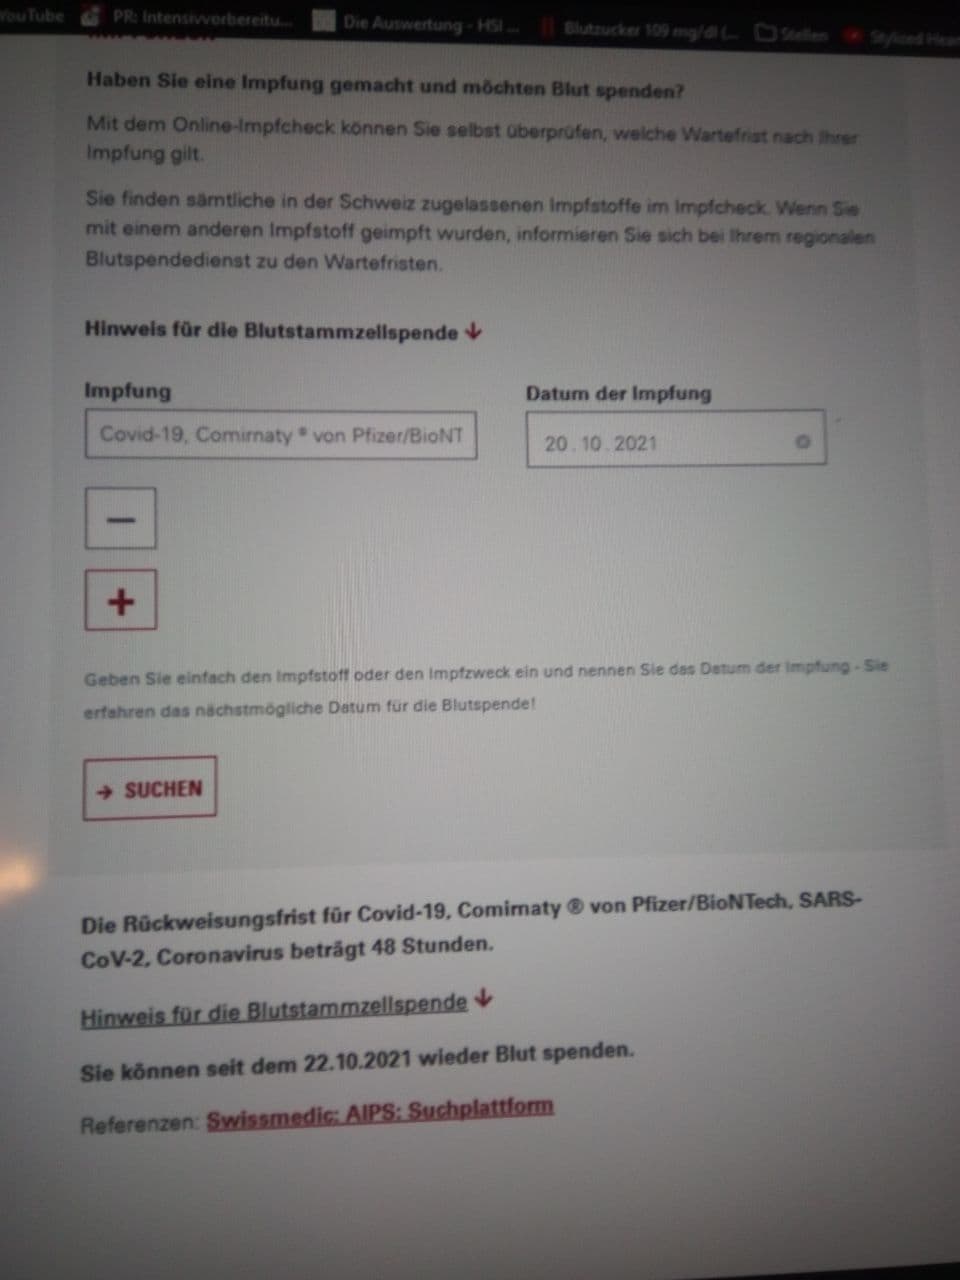

Medizinisches Blut spenden 17.1.2022:

Swissmedic Suchplattform meint: GENgeimpfte 48 Stunden

ohne Nebenwirkungen dürfen Blut spenden

Impfschäden Schweiz Coronaimpfung, [17/01/2022 08:49 A.M.]

https://t.me/Impfschaden_Corona_Schweiz/37470

hoi mara und team

zur frage ob geimpfte blut spenden dürfen...

eindeutig ja

Foto 1: https://t.me/Impfschaden_Corona_Schweiz/37471

Foto 2: https://t.me/Impfschaden_Corona_Schweiz/37472

Medizinisches Blut spenden 17.1.2022: Swissmedic

Suchplattform meint: GENgeimpfte 48 Stunden ohne

Nebenwirkungen dürfen Blut spenden Foto 1 [39]

Medizinisches Blut spenden 17.1.2022: Swissmedic

Suchplattform meint: GENgeimpfte 48 Stunden ohne

Nebenwirkungen dürfen Blut spenden Foto 2 [40]